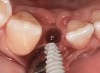

The crown and screw-retained custom abutment were removed, and a surgical cover screw was placed into the implant, thereby allowing spontaneous gingival augmentation in situ (Figure 33 and Figure 34). Note that the lingual aspect of the implant site was significantly more coronal than the labial aspect, which was positive because the defect would be limited to a facial–lingual defect. A fixed RBR bridge was cemented on the adjacent teeth and used as a tooth-supported transitional provisional restoration (Figure 35). A few weeks were allotted to let the soft tissue heal and migrate around the cover screw (Figure 36) to see if there would be complete coverage, thereby allowing a soft-tissue augmentation procedure to be performed with primary flap closure as in clinical scenario No. 2. The major obstacle in achieving a positive tissue response was that the implant depth was also deficient because the implant–abutment connection was at the level of the free gingival margin. It was decided that the best treatment option would be to remove the implant. A high-powered reverse-torque device (Fixture Remover Kit, NeoBiotech, www.neobiotechus.com) was used to remove the implant atraumatically (Figure 38 through Figure 41). The implant socket was allowed to heal for several months not unlike an extracted tooth (Figure 42). A new implant was placed in a better position from both a restorative and esthetic perspective (Figure 43), and after a few months of healing, a new crown was made (Figure 44). A satisfactory functional and esthetic result was achieved (Figure 45 and Figure 46) without employing pink porcelain.

Fig 38. A reverse-torque screw was placed into the implant.

Figure 38

Fig 39. A counter-torque device was placed over the reverse-torque screw.

Figure 39

Fig 40. The implant was easily unscrewed within minutes in a minimally invasive manner with less trauma to the surgical site.

Figure 40

Fig 41. The removed implant with some apical bone adherent to the surface.

Figure 41

Fig 42. Two months of healing was allowed post-implant removal to create enough soft tissue for implant replacement coverage.

Figure 42

Fig 43. A full thickness flap was raised to place a new 3.25-mm implant into tooth No. 26 area in a single-stage protocol.

Figure 43

Fig 44. A new metal-alloy abutment was fabricated for the narrow-diameter implant with a cement-retained metal-ceramic crown.

Figure 44

Fig 45. The definitive crown tooth No. 26 seated in place and provisionally cemented. The recession defect was eliminated with the removal and replacement of a new implant in the proper position.